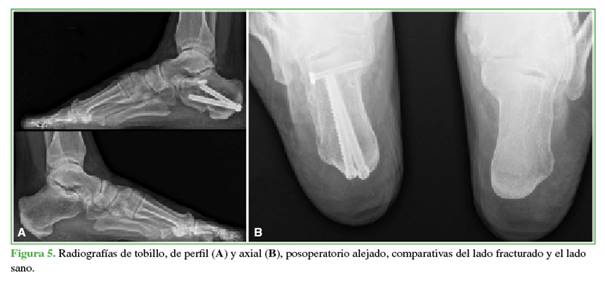

La cantidad y orientación de los tornillos de 6,5/7 mm dependerá de los trazos de fractura. El objetivo de estos es solidarizar la tuberosidad mayor con el cuerpo del calcáneo y con la tuberosidad menor, generando además un “andamiaje” que le brinde estabilidad a la carilla articular posterolateral (Figuras 4-6).

La media del ángulo de Böhler mostró diferencias significativas entre el calcáneo contralateral sano (30,76° ± 5,71°) y la determinación preoperatoria (14,05° ± 6,60°). Sin embargo, las diferencias entre el lado contralateral sano (30,76° ± 5,71°) y los valores posoperatorios, tanto inmediato (29,50° ± 5,96°) como alejado (29,86° ± 6,51°), fueron mínimas. Asimismo, se consideraron los percentiles 25, 50 y 75. Las pruebas de la t de Student para muestras independientes confirmaron que no hubo diferencias estadísticamente significativas entre las mediciones en el calcáneo contralateral sano y los valores posoperatorios inmediato (intervalo de confianza del 95% [IC95%], p <0,571, d = 0,216) y alejado (IC95%, p <0,700, d = 0,147), mientras que sí hubo diferencias significativas con el valor preoperatorio (IC95%, p <0,001, d = 2,708).

La media del ángulo de Gissane resultó con diferencias entre el calcáneo contralateral sano (119,03° ± 6,99º) y el valor preoperatorio (110,31º ± 10,01º). Sin embargo, entre el lado contralateral sano (119,03° ± 6,99º) y las determinaciones del posoperatorio inmediato (118,85 ± 7,54) y el alejado (119,00 ± 7,43), la diferencia no fue significativa. Las pruebas de la t de Student para muestras independientes confirman que no hubo diferencias estadísticamente significativas entre el calcáneo contralateral sano y los valores posoperatorios inmediato (IC95%, p = 0,948, d = 0,0248) y alejado (IC95%, p = 0,992, d = 0,004), mientras que sí hubo diferencias significativas con el valor preoperatorio (IC95%, p = 0,013, d = 1,010).

La media de la longitud del calcáneo arrojó diferencias mínimas entre el calcáneo contralateral sano (77,61 ± 8,25), el valor preoperatorio (76,01 ± 8,47), los valores posoperatorios inmediato (78,26 ± 8,01) y alejado (76,99 ± 7,56). Las pruebas de la t de Student para muestras independientes confirman que no hubo diferencias estadísticamente significativas entre el calcáneo contralateral sano, el valor preoperatorio (IC95%, p = 0,617, d = 0,191) y los valores posoperatorios inmediato (IC95%, p = 0,835, d = -0,080) y alejado (IC95%, p = 0,836, d = 0,078).

La media del ancho del calcáneo mostró diferencias entre el calcáneo contralateral sano (36,94 ± 4,09) y el valor preoperatorio (44,13 ± 9,36). Sin embargo, entre el lado contralateral sano (36,94 ± 4,09º) y los valores posoperatorios inmediato (39,17 ± 4,77) y alejado (38,99 ± 5,16), la diferencia fue poca.

La TC posoperatoria reveló 9 reducciones anatómicas y 5 reducciones casi anatómicas. La media del puntaje de la AOFAS fue de 84,14 ±11 y la mediana, de 86,00 (Tabla).

La mejor exposición de la fractura lograda con el AbLA debería proporcionar mejores reducciones; no obstante, los tornillos canulados asociados al AbST resultaron ser más predecibles para mejorar los ángulos de Gissane y Böhler. Pitts y cols.23 compararon 51 FCDA tratadas por un AbST y tornillos canulados con 23 fracturas tratadas por un AbLA y no hallaron diferencias significativas. Wang y cols.21 sostienen que los tornillos canulados aseguran mejores reducciones. En nuestra serie, tanto el ángulo de Gissane como el de Böhler en el posoperatorio alejado no tuvieron diferencias significativas con respecto al calcáneo contralateral sano, por lo que concluimos en que la menor exposición fracturaria no conduce a defectos de reducción. Sanders y cols. recomiendan la TC para la evaluación posoperatoria de la reducción de la FAPLc y clasificarlas según la altura del escalón remanente. Consideran que una reducción es anatómica cuando el escalón no es superior a 1 mm y casi anatómica cuando el escalón mide entre 1 y 3 mm.6 El AbST nos permitió lograr 9 reducciones anatómicas y 5 reducciones casi anatómicas, no registramos escalones >2 mm. Creemos que la visualización de la FAPLc que ofrece el AbST es suficiente para una correcta reducción.